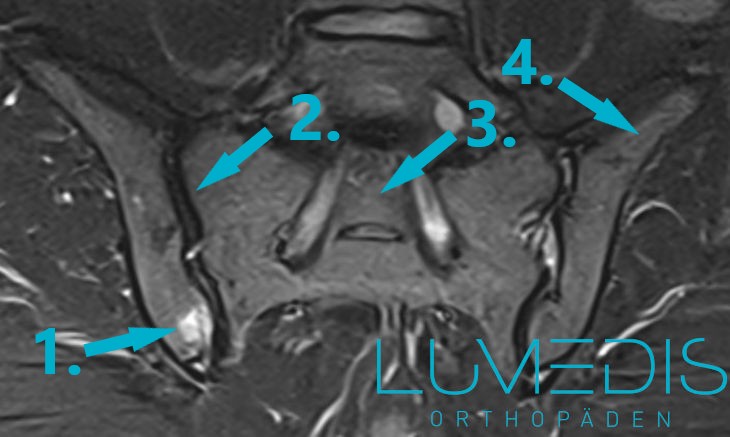

Abbildung eines Bandscheibenvorfall mit Nervenwurzelkompression links